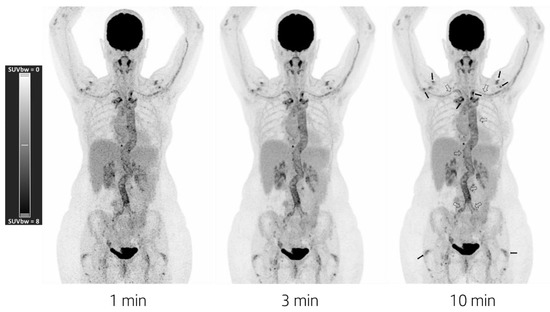

18F-FDG-PET/CT showed physiologic uptake in the brain, salivary glands, mediastinum, liver, spleen, kidneys, and bladder. Pathologic uptake was seen at the walls of the aorta, brachiocephalic trunk, common carotid arteries, and subclavian arteries (Figure 1). No other abnormal uptake was seen—neither in the chest and neck—nor did a low-dose CT show any infiltrate, ground glass, or nodular pathology. The pathologic uptake surrounding the aorta continued into the abdominal aorta and the common iliac arteries, in combination with a pathologic FDG uptake surrounding the sternoclavicular joints, acromioclavicular joints, shoulder joints, greater trochanters, and spinous processes; this is highly suggestive of GCA with PMR.

Figure 1. Maximum intensity projection PET images acquired for 1 min (left), 3 min (middle), and 10 min (right). Images were reconstructed using a vendor-recommended clinically optimized protocol for optimal image quality, consisting of 3D OSEM with 4 iterations, 5 subsets, a matrix size of 440 × 440 × 708 with a voxel size of 1.6 × 1.6 × 1.5 mm3, time-of-flight application, resolution modelling, and no filtering. Data were acquired using a maximum ring difference of 85. In all three images, ranging from very fast to standard acquisition time, one can see the following typical features of GCA and PMR: increased uptake in the aortic wall; the common iliac arteries; and the subclavian and axillary arteries due to GCA activity (hollow arrows in right image), and moderately to highly increased uptake around the shoulders, sternoclavicular joints, acromioclavicular joints, and greater trochanters due to PMR activity (filled in black arrows right image).